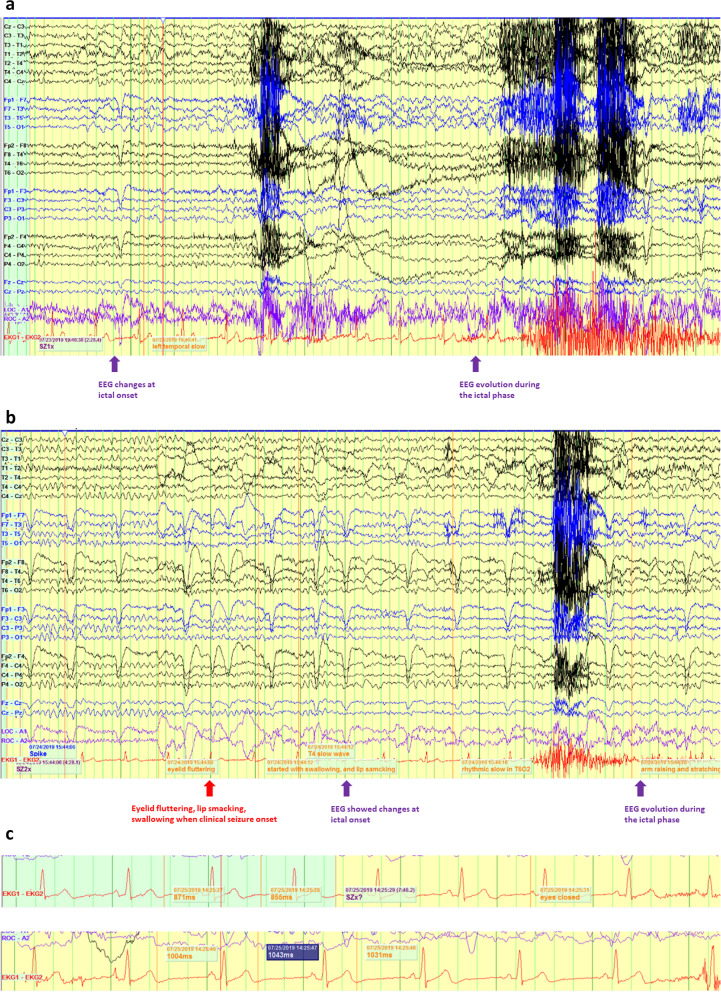

Case presentation: We present a 35-year-old man with a history of focal-onset seizures with impaired consciousness since his mid-20 s. He developed different types of seizures for 2 years, described as tonic seizure and atonic seizure (drop attack). During such clinical events, he suffered from falls and cardiac arrest. However, thorough cardiac electrophysiology and imaging workup failed to reveal a cardiac etiology. Subsequent video electroencephalograph (EEG) monitoring was performed, and ictal bradycardia and ictal asystole were discovered. A cardiac pacemaker was implanted, and at 3-year follow-up, the patient did not suffer more atonic seizures, or falls. Genetic tests discovered a de novo variant of Adhesion G Protein-Coupled Receptor V1 (ADGRV1), which may provide a clue for the patient's ictal asystole and the increased risk of SUDEP.

Conclusions: Considering the important impact of ictal bradycardia and asystole on the morbidity and potential mortality of epileptic patients, it is important to simultaneously utilize EEG and electrocardiogram to confirm the diagnosis. This case report highlights the link between the de novo variant of ADGRV1 and the ictal bradycardia/asystole phenotype and implicates the importance of genetic testing in adult epilepsy patients.